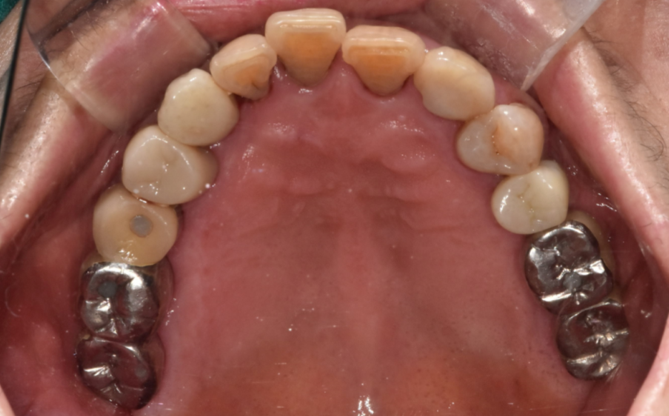

<완성 사진>

240118

여기저기 충치도 있고

뿌리만 남아있었는데 싹~ 치료하신 모습을 보니

뿌듯합니다.

깔끔해졌습니다.